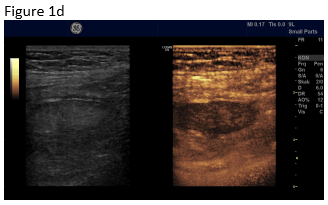

Figure 1: B-mode ultrasound using low frequency (a) and high frequency (b) revealed an isoechoic mass with a hypoechoic circumference. The mass was not adher-ent to the colon. Contrast enhanced ultrasound using low frequency (c) and high frequency (d) revealed that it was a non-enhancing segment of the omentum. Strain elastography showed that the lesion was stiffer than its sur-rounding tissue.